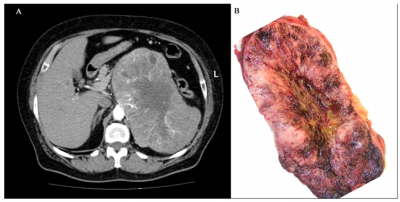

- טומוגרפיה ממוחשבת - בדיקה המאפשרת הדגמה טובה של יותרת-הכליה והשאת, והיא בדיקת הבחירה להדגמת יותרת-הכליה. חסרונה הוא בכך שהיא מדגימה גושים הגדולים מ- 1 ס"מ ואינה יכולה להבחין בין שאת פעילה לזו שאינה פעילה (תמונה 6.14- 7).

7% מהחולים סובלים משאת ממאירה. השאת היא בעלת קפסולה בצבע חום-צהבהב עד חום-אדמדם. פלאומורפיזם, חדירה לכלי הדם, הלימפה ולתוך הקפסולה מופיעים, אולם אינם בהכרח סימן לממאירות. רק גרורות מרוחקות מעידות על ממאירות.